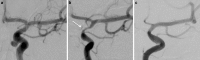

Results: In total, 205 patients (147 female, 71.7%; median age 57 years), with 223 saccular aneurysms were treated with p64 and had at least 9 months of digital subtraction angiography (DSA) follow-up completed. There was no DSA follow-up available in 8 patients. ISS of any degree at any time was recognized in 65/223 (29.1%) of all target aneurysms. The maximal degree of lumen loss was <50% in 40 lesions (17.9%), 50-75% in 19 lesions (8.5%), and >75% in 6 lesions (2.7%). ISS did not cause a focal neurological deficit in any patient. No progression from stenosis to occlusion was observed. Balloon angioplasty was performed in 1 lesion and was well tolerated. In 56 lesions (84.8%), a significant reduction of ISS occurred spontaneously, 2 mild stenoses remained stable, and for 6 lesions the long-term follow-up is pending.

Conclusion: Treatment with p64 is associated with an overall rate of 8.5% moderate ISS (50-75%) and 2.7% severe ISS (>75%), which is comparable with the rate of ISS reported in the literature for other flow diverting stents. There is a tendency for ISS to spontaneously improve over time.